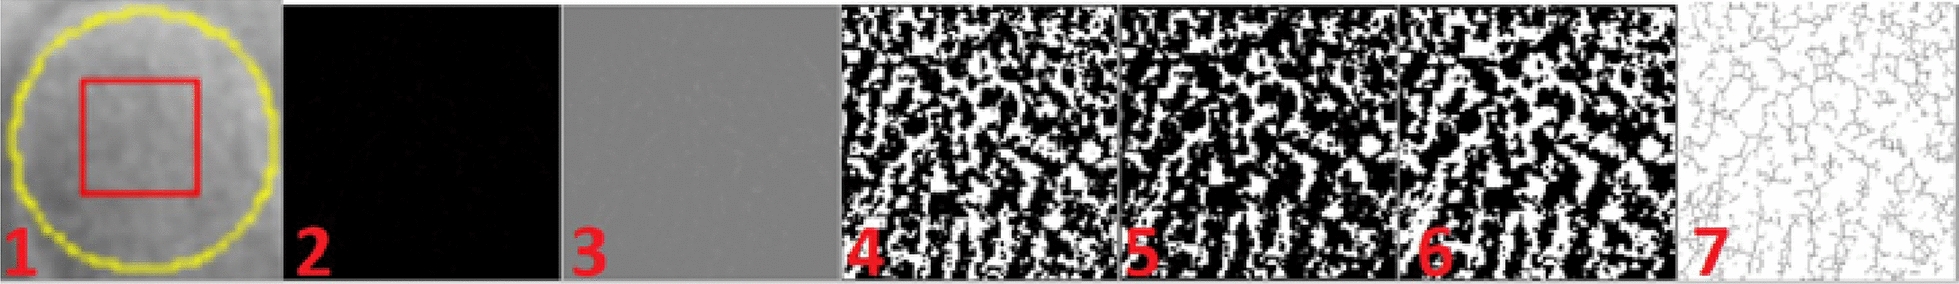

Methods: A retrospective, age- and gender-matched, 3-year longitudinal comparison was performed using 120 panoramic radiographs from 60 individuals (30 PHPT; 30 controls). Each participant contributed baseline and 3-year images (mean interval: 3.26 ± 0.13 years). Radiomorphometric indices (SI, MI, AI, PI, PMI) and FD from three standardized regions of interest (ROI1: condyle; ROI2: angle; ROI3: mental) were measured. Intra-observer reliability was excellent (ICCs 0.80-0.96). Between-group and within-group comparisons used Mann-Whitney U and Wilcoxon signed-rank tests (two-sided, p < 0.05).

Results: The antegonial index (AI) was lower in PHPT than controls at baseline (3.26 ± 0.43 vs. 3.62 ± 0.81 mm; p = 0.034) and remained lower at 3 years (3.24 ± 0.35 vs. 3.55 ± 0.43 mm; p = 0.050). Other indices (SI, MI, PI, PMI) showed no between-group differences at either timepoint and no significant within-group change (all p > 0.05). FD analysis showed a lower ROI2 (mandibular angle) value in PHPT at baseline (p = 0.050) and a significant difference at 3 years (p < 0.01); ROI1 and ROI3 did not differ between groups at either timepoint and exhibited no temporal change (all p > 0.05).